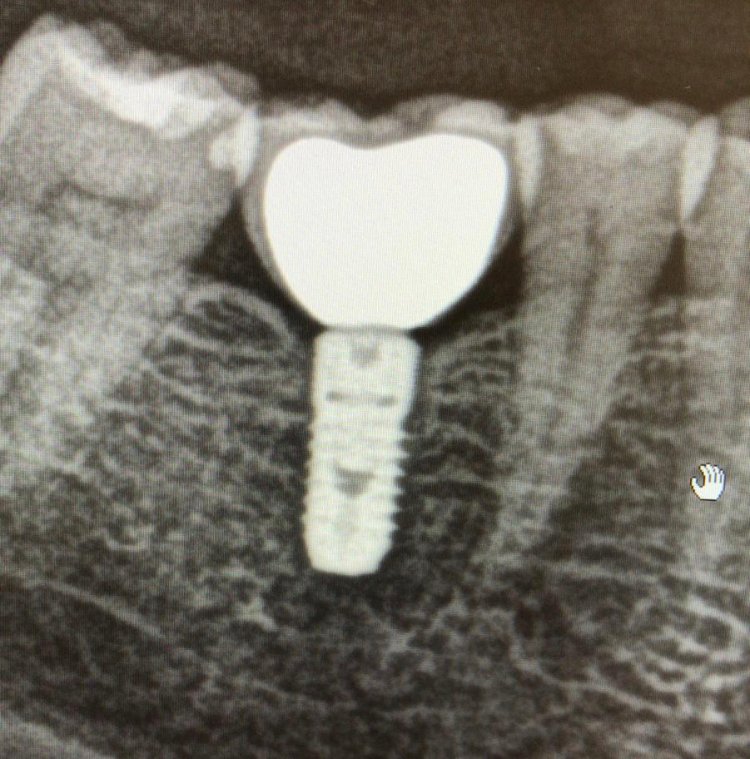

El implante 46 no se cual es

Paciente se realizó implante 46 hace unos 10 años, acude con tornillo interno fracturado. Necesito saber que implante es para su rehabilitación. Muchas Gracias!